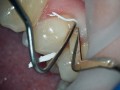

Zmodyfikowana technika ściany z tkanek miękkich (soft tissue…